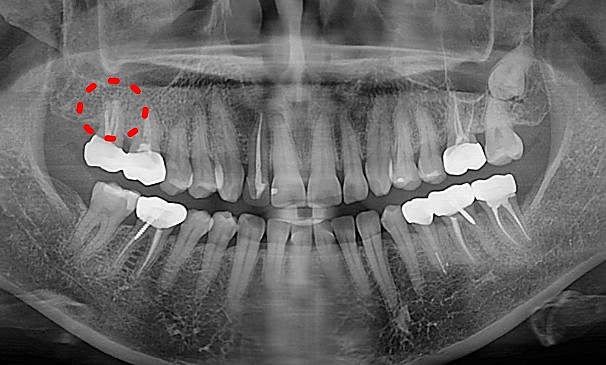

자가치아 재 식립술란?

자가치아재식립술이란 치아에 염증이 심하거나 신경치료 된 치아에 어떤 문제가 생겼을 때

해당 치아를 조심스럽고 안정적으로 발치한 후, 구강 밖에서 염증이나 병든 부분을 깨끗하게 제거 하고

뽑았던 치아는 특수 재료로 처리한 다음에 원래 있었던 자리로 다시 조심스럽게 식립하여 치아를 살리는 치료법입니다.